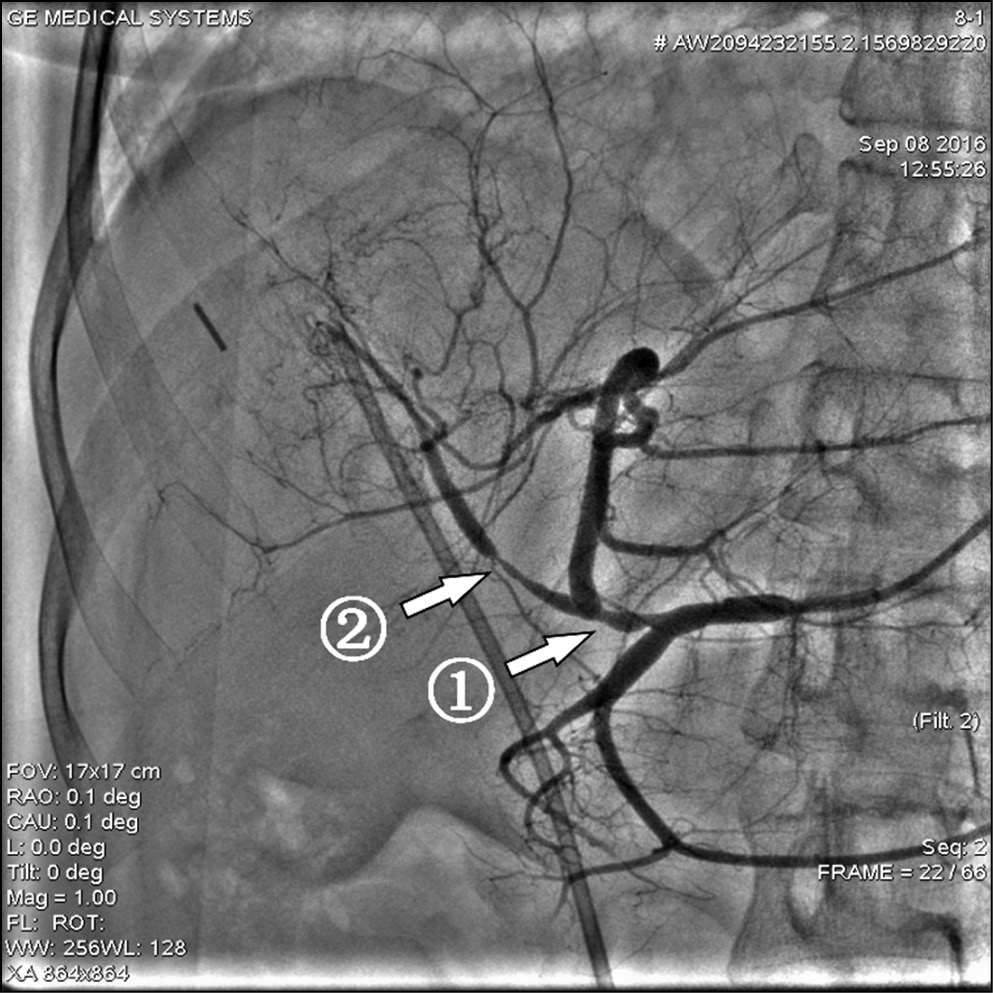

Типичная артериальная анатомия печени была отмечена у 26 (86,7%) исследуемых больных с вторичным неоперабельным метастатическим поражением печени, однако у одного пациента с типичным вариантом кровоснабжения был выявлен критический стеноз чревного ствола, еще у одного — окклюзия чревного ствола (рис. 1, 2). Таким образом, только 24 (80%) обследованных пациента имели типичный неосложненный вариант кровоснабжения печени. Другие (атипичные) варианты кровоснабжения печени наблюдались в 4 (13,3%) случаях. Следует подчеркнуть, что особенности анатомического строения сосудов печени не повлияли на результативность и завершенность процедуры ХЭПА благодаря возможности использования микрокатетерной техники для суперселективного введения микросфер (см. рис. 1, 2).

Рис. 1. Вариант кровоснабжения печени при окклюзии чревного ствола

Примечание. 1 — чревный ствол, 2 — верхняя брыжеечная артерия, 3 — коллатеральное заполнение бассейна чревного ствола из верхней брыжеечной артерии через a. pancreatiсoduodenalisinferior и ретроградно через а. pancreatiсoduodenalissuperior и a. gastroduodenalis.

Рис. 2. Селективная катетеризация микрокатетером сегментарных ветвей правой печеночной артерии при окклюзии чревного ствола

Примечание. 1 — ангиографический катетер 5F в устье верхней брыжеечной артерии, 2 — микрокатетер, проходящий из верхней брыжеечной артерии через a. pancreatiсoduodenalisinferior и ретроградно через а. pancreatiсoduodenalissuperior и a. gastroduodenalis в правую печеночную артерию, 3 — кончик микрокатетера в сегментарной ветви правой печеночной артерии.